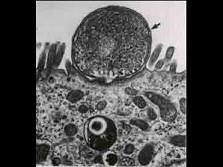

问题 图示关隐孢子虫,下列关于其生活特性的说法正确的是 ( )

选项 A.专性细胞外生长 B.专性细胞内生长 C.细胞内外均可生长 D.细胞内的胞浆外生长 E.以上均不是

答案 B